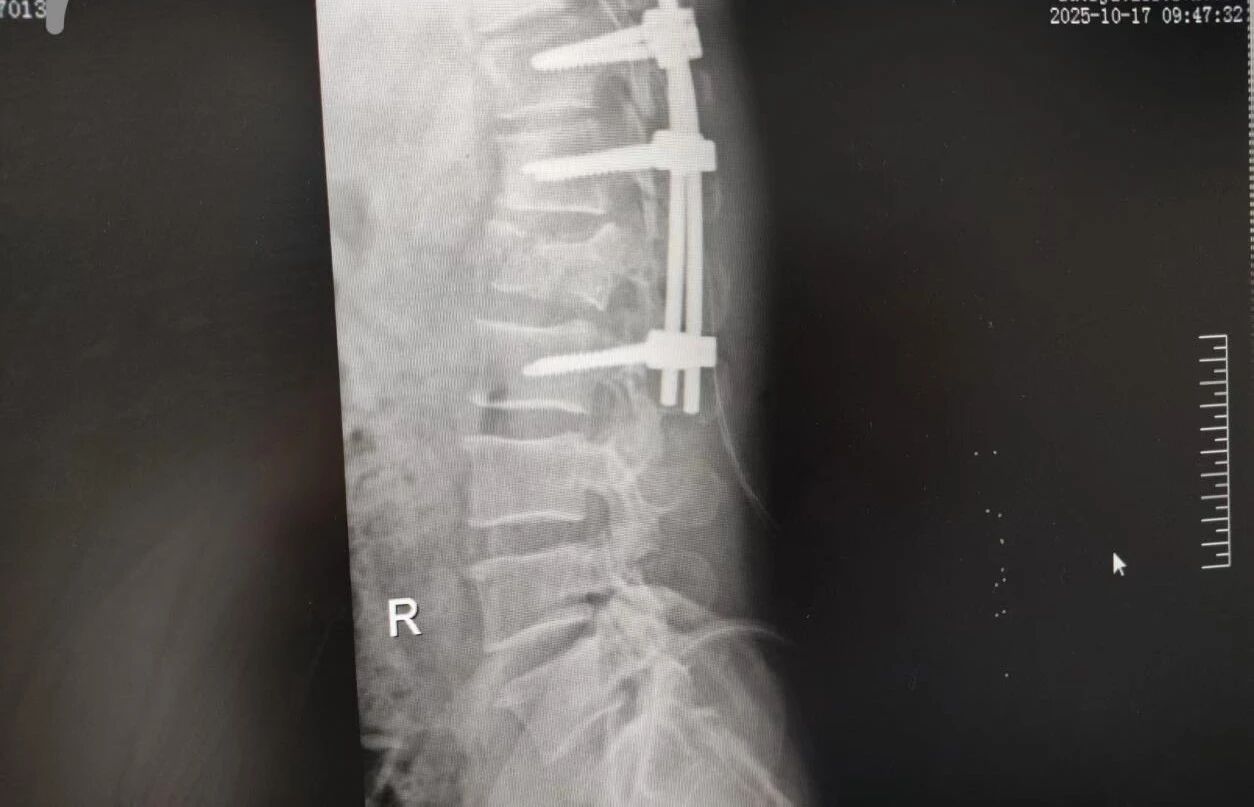

針對腰椎傷情,骨科竇志剛醫(yī)生團(tuán)隊(duì)緊急開展腰 1 椎體爆裂性骨折切開復(fù)位內(nèi)固定術(shù) + 椎板切除減壓術(shù)。手術(shù)室、麻醉科無縫銜接開通綠色通道,手術(shù)團(tuán)隊(duì)快速就位,術(shù)后患者下肢活動恢復(fù)自如。